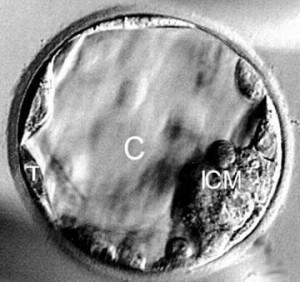

You looked like this once…

Probably the main difficulty is that the early embryo does not look like a human being and it is so tiny. It is hard to see how this tiny being could be the same person as a baby or as an adult. It is just a clump of cells.

The embryo is indeed a clump of cells, but it is a very special clump of cells. It is a developing human being. An embryo does not look like an adult human being but it looks like a human being is supposed to look in the first few days and weeks of life.